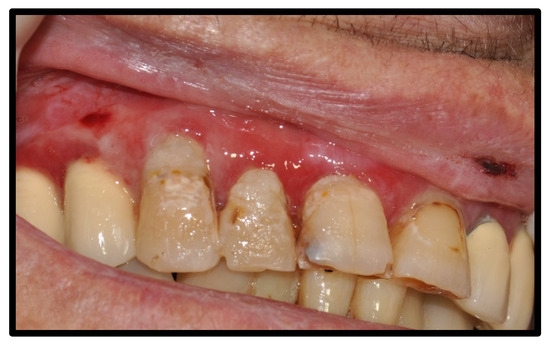

| OLP/lichenoid reaction (3 were exacerbations of previous autoimmune disease) | 12 | 50.00 | |

| Management | Costicosteroid mouthwash, with good response | ||